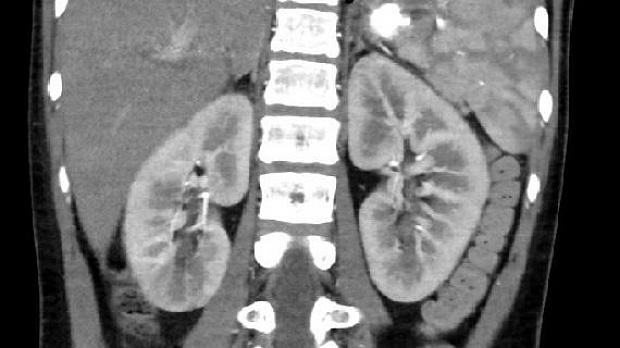

Пациент К. 13 лет с тяжелой травмой печени. В фундальном отделе по задней стенке определяется четко ограниченный участок гиперемированной, отечной, неровной слизистой оболочки с белесоватым налетом. Локализация процесса объясняется тем, что пациент длительное время находился на лечении в отделении ОРИТ (в горизонтальном положении), получал эрадикационную терапию (в том числе Де-Нол) в рамках комплексного лечения. При КТ ОБП в паренхиме правой доли печени - две металлические клипсы (результат эмболизации). А в просвете желудка определяется включение металлической плотности. У врачей возникло подозрение на проглоченное инородное тело, однако это было исключено предшествующей ЭГДС, на которой, кроме локального участка инфильтрации, инородных тел выявлено не было.